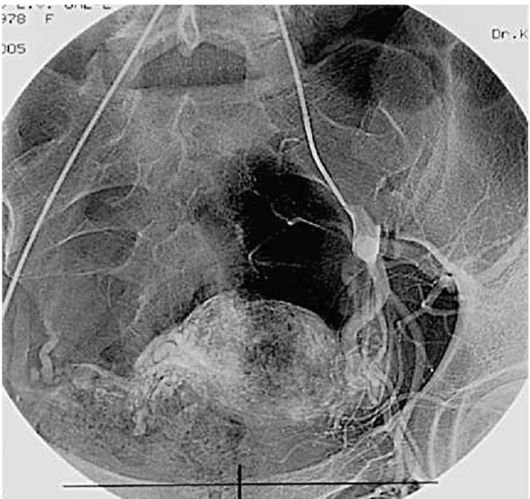

Тазовые спайки часто встречаются у женщин с обширным эндометриозом, который не лечился. Спайки также могут образовываться после кесарева сечения или других видов открытой хирургии и могут быть результатом инфекций. Рубцовая ткань может расти между двумя органами в области таза и вызывать сильную тазовую боль. Тазовые спайки могут возникать вокруг мочевого пузыря, кишечника, мочеточника, матки и яичников.

Хирургические процедуры, такие как миомэктомия и хирургия эндометриоза, также могут приводить к образованию спаек. Спайки чаще встречаются после открытой операции (это означает, что хирург использовал 8-дюймовый разрез, чтобы получить доступ к полости таза), чем после лапароскопической операции. Риск образования спаек увеличивается с увеличением количества крупных операций на органах брюшной полости и таза, а послеоперационная инфекция или кровотечение могут привести к образованию спаек из-за усиления воспаления в процессе заживления.

Тазовые спайки могут влиять на способность женщины зачать и выносить ребенка до срока, особенно тазовые спайки или рубцовая ткань, связанные с эндометриозом.

Эта рубцовая ткань во многих случаях может быть совершенно бессимптомной. Однако, когда это вызывает бесплодие, боль или проблемы с желудочно-кишечным трактом, такие как вздутие живота и запор, женщина может рассмотреть возможность проведения процедуры, называемой резекцией тазовых спаек.